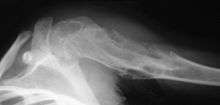

On radiographs, streaks of low density are seen projecting through the diaphyses into the epiphyses of the long bones, due to ectopic cartilage deposits. With age, the cartilage may calcify in the typical "snowflake" pattern.

X-ray showing enchondromas localized in the humerus of a 37-year-old patient affected with Ollier disease